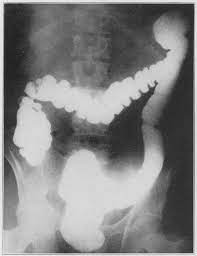

This occurs when small amounts of stool get trapped in the pouches. He looks as if he should be sitting in the stands and eating a hot dog or two or three while he watches the game. Most people fail to lose weight due to overeating. If you have also leg swelling heart function. Redundant colon sometimes referred to as tortuous colon is a term used to describe when someone has a colon thats longer than normal. Megacolon is the term used for an abnormally enlarged colon.

A case of a redundant colon is seen mostly in those with a genetic risk factor for this condition. It can cause severe constipation. Small pouches that form along the exterior of the colon are called diverticula and when theyre present a person has diverticulosis. Ulcerative colitis UC and Crohns disease. Megacolon can be congenital and is often hereditary or can gradually develop over many years of poor diet constipation andor laxative abuse. They inflame the colon and can cause belly pain weight.